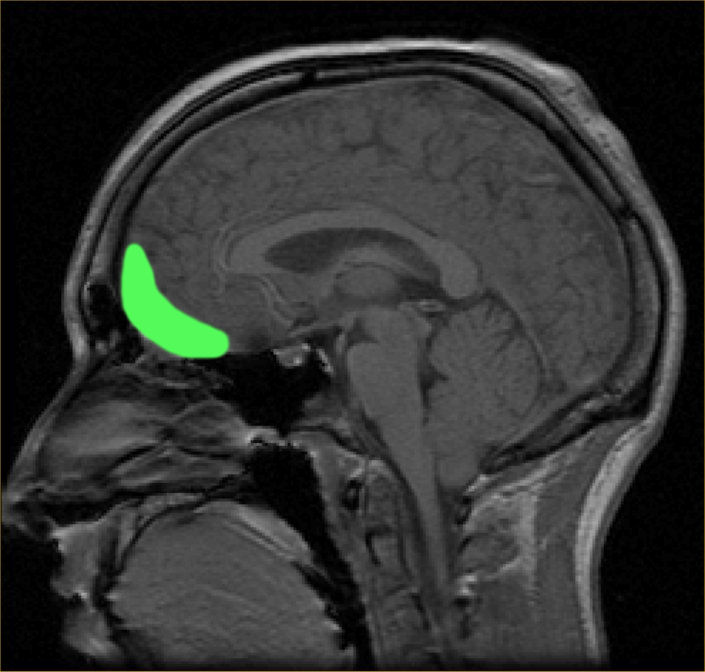

6. 1. 전전두피질 (Prefrontal cortex)

전전두피질은 색깔 있는 물체의 지각, 의사 결정, 기억과 관련된 역할로 알려져 있었다. 최근 연구에 따르면 시각적 자극의 매력을 판단하는 것과 같은 미적 과제 중에 활성화되기 때문에 의식적인 미적 경험과도 관련이 있는 것으로 나타났다. 이는 시공간적 기억을 필요로 하는 판단이 필요하기 때문일 수 있다.[42] Zeki와 Kawabata의 연구에서는 내측 안와전두피질(mOFC)이 그림의 아름다움을 판단하는 데 관여한다는 사실이 밝혀졌다. 아름답다고 생각하는 그림을 볼 때 이 영역의 활성이 높게 나타난다. 이 영역은 음악[54], 도덕[55], 수학적 아름다움[56] 등 다양한 출처에서 파생된 아름다움의 경험 중에 활성화된다.[53] 숭고함의 경험은 뇌 활동의 다른 패턴을 초래한다.[57] 미적 판단과 지각적 판단은 동일한 뇌 영역에서 활동을 유도하지만, 활동 패턴은 다르며, 미적 판단에는 mOFC가 관여하지만 지각적 판단에는 관여하지 않는다.[58] 못생겼다고 생각하는 그림을 볼 때는 별도의 구조가 활성화되지 않는다. 따라서 안와전두피질의 활성 강도 변화가 아름다움(더 높은 활성) 또는 추함(더 낮은 활성)의 결정과 상관관계가 있다는 가설이 제기되었다.

운동 피질의 활성은 정반대의 패턴을 보였다.[59] 내측 OFC는 텍스트나 예술 작품에 대한 설명과 같이 제시되는 맥락에 따라 미학에 반응한다. OFC가 미각, 후각, 시각 등 다양한 감각 양식에 걸쳐 부여된 쾌락적 가치와 연관되어 있다는 증거는 OFC가 자극의 가치를 평가하는 공통 중심지임을 시사한다.[45] 이러한 영역에 대한 미학적 지각은 뇌의 보상 시스템 활성화와 관련이 있을 것이다.

배외측 전전두피질(PDC)은 아름답다고 여겨지는 자극에 의해서만 선택적으로 활성화되는 반면, 전전두피질 전체는 즐겁거나 불쾌한 자극을 판단할 때 모두 활성화된다.[60] 전전두피질은 시각 예술에 훈련받지 않은 시청자들의 미적 지각 과정에서 인지 및 지각 메커니즘에 주의를 기울이도록 하는 역할을 할 수 있다.[22] 즉, 인지의 상향식 제어를 통해 미적 지각에 관여한다. 외측 전전두피질은 고차원적인 자기 참조 처리 및 내부적으로 생성된 정보 평가와 관련이 있다. 좌측 외측 PFC, 즉 브로드만 영역 10은 미적 지향점에서 예술에 접근할 때 내부적으로 생성된 목표를 실행하는 데 주의를 기울이는 역할을 할 수 있다.[22]